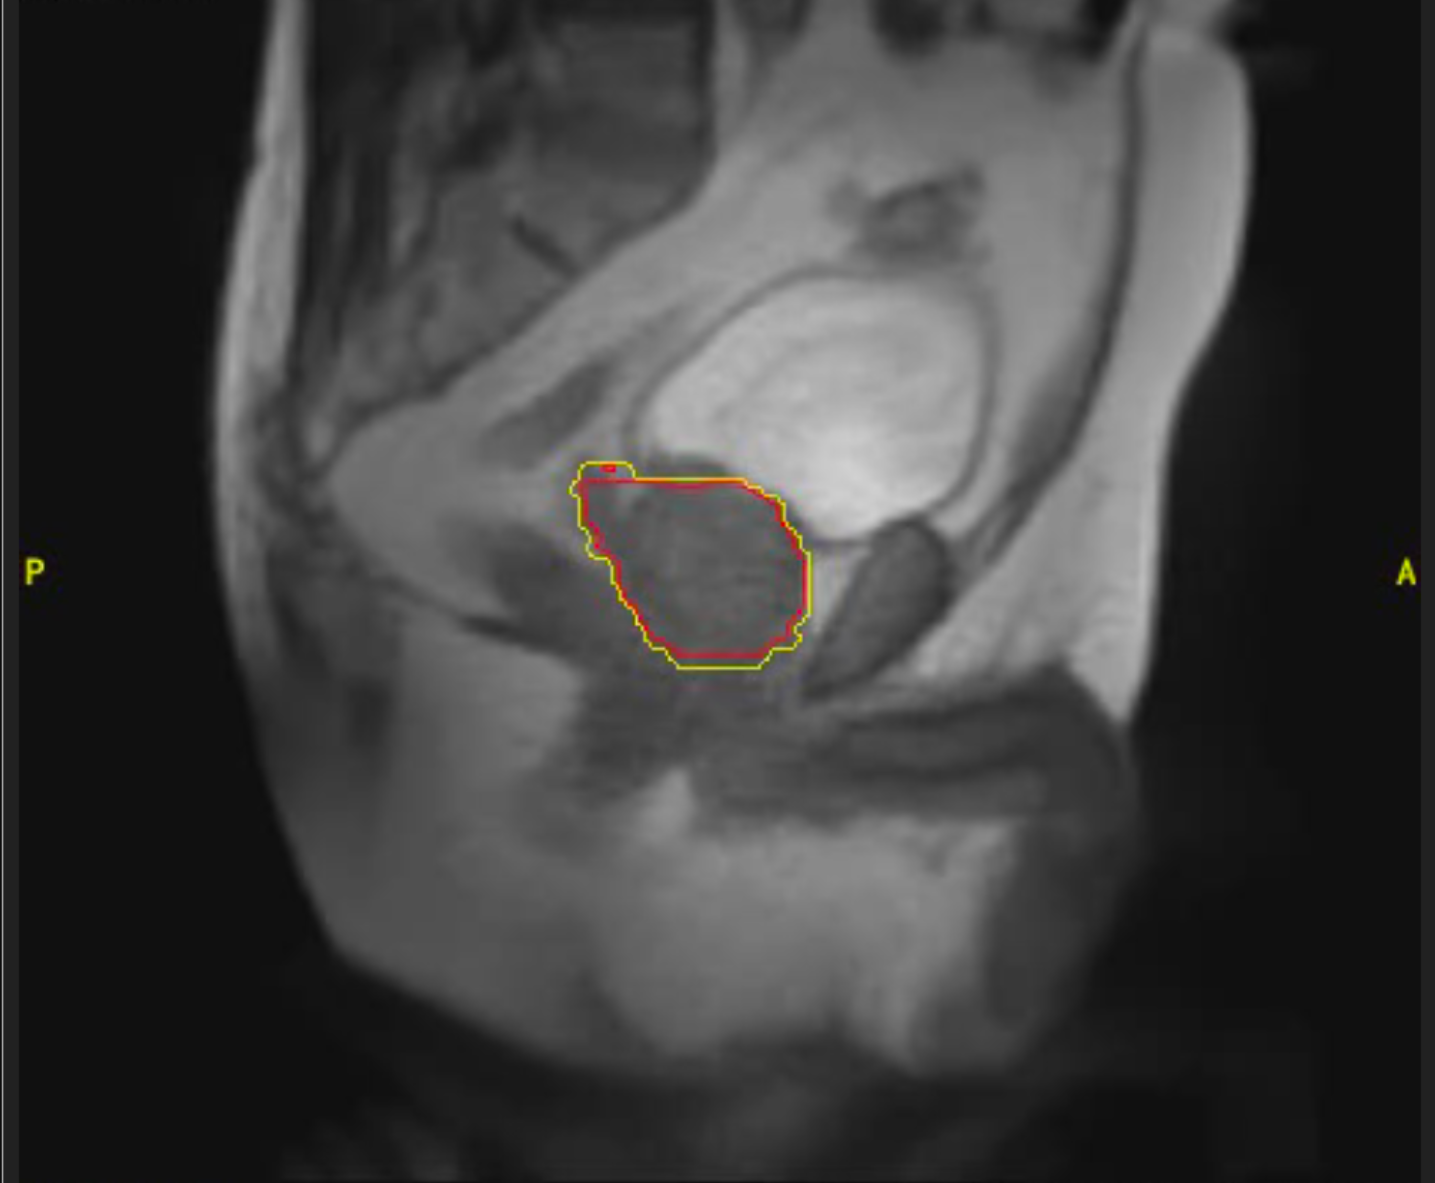

Cáncer de páncreas

Mujer de 46 años con diagnóstico de adenocarcinoma de cabeza de páncreas localizado. Recibe tratamiento con quimioterapia durante 5 ciclos y seguidamente radioterapia con intención radical en Acelerador Lineal con Resonancia (MRIdian): 5 fracciones en 5 días. Presentó buena tolerancia al tratamiento, sin efectos adversos destacables y tras 3 meses de finalizado el mismo se encuentra con enfermedad estable.

Imagen 1

Imagen 2

Imagen 3

Imagen 4